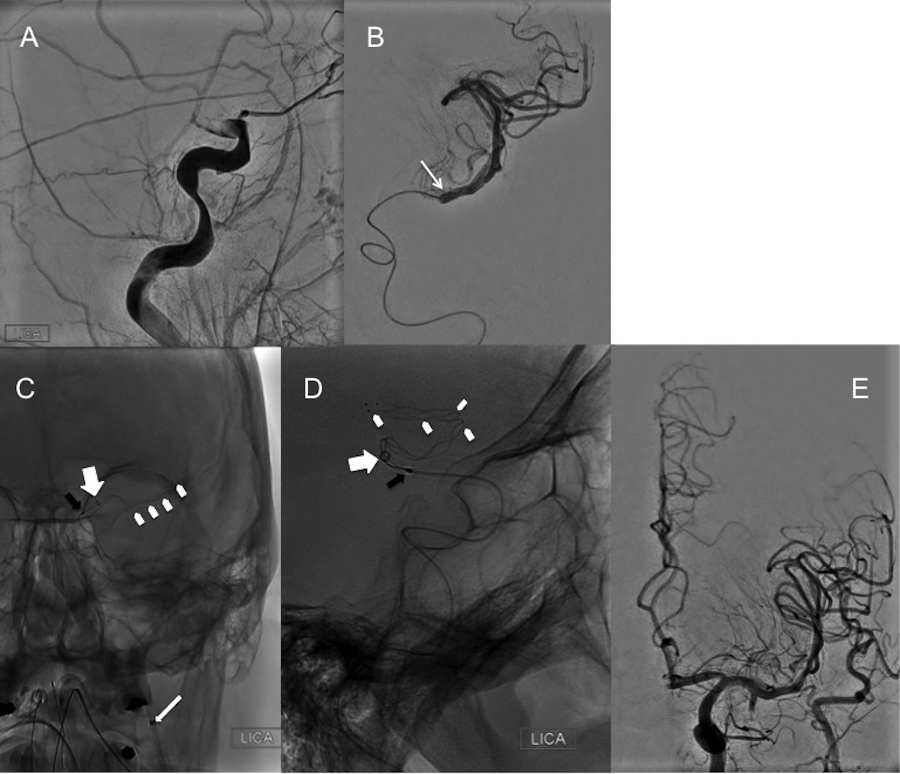

Case 2

A 59-year-old female with pre-stroke mRS 1 presented to the Emergency Department after an abrupt onset of left-sided hemiplegia and left hemineglect, with an NIHSS of 17. No rtPA was given as the time of stroke/symptom onset was unknown. CTA of the head and neck demonstrated occlusion of the right ICA terminus extending into the ipsilateral M1 and A1 segments (“T” occlusion). A hyperacute magnetic resonance image (MRI) of the brain demonstrated restricted diffusion within the right basal ganglia. Prior to any intervention, her stroke symptoms spontaneously improved to an NIHSS of 10 by the time the MRI was obtained. The patient was then referred to our service for mechanical thrombectomy. Since the patient was agitated, the procedure was carried out under general anesthesia. A DSA of the head confirmed the CTA findings (Figure 2A). The cavernous carotid artery of this patient was a type III (moderate), defined by the posterior deflection of the posterior genu, giving it a buckled appearance [10]. The triaxial assembly consisted of a 9 Fr Cello™ (ev3) for BGC, the Arc™ catheter (Medtronic) as the intracranial AC, and the Excelsior® XT-27® microcatheter (Stryker Neurovascular), which was, in turn, navigated over a Synchro-2® microwire (Stryker Neurovascular) into the right middle cerebral artery (MCA). The microcatheter was positioned just beyond the distal right M1 segment. A 6 x 20 mm Solitaire™ 2 stent-retriever (ev3) was deployed, spanning the distal right M1 down to the ipsilateral supraclinoid ICA. The Arc™ catheter was further navigated intracranially into the supraclinoid ICA at the proximal aspect of the clot (Figures 2B-2C). After the first thrombectomy pass, follow-up angiograms demonstrated recanalization of the supraclinoid ICA and right anterior cerebral artery (ACA) with residual occlusion of the right M1 segment. In a similar fashion, with the same triaxial assembly, the stent-retriever was deployed spanning the entire length of the right M1. The Arc™ catheter was again positioned against the proximal aspect of the clot. After the second thrombectomy pass, follow-up angiograms demonstrated complete recanalization of the right MCA and right ACA with a TICI 3 (Figures 2D-2E). The patient was transferred to the neurointensive care unit where, at POD 1, she had recovered to a 4/5 left hemibody strength with some mild dysarthria. By POD 3, the patient was transferred to a rehabilitation facility for further management with an NIHSS of 3.